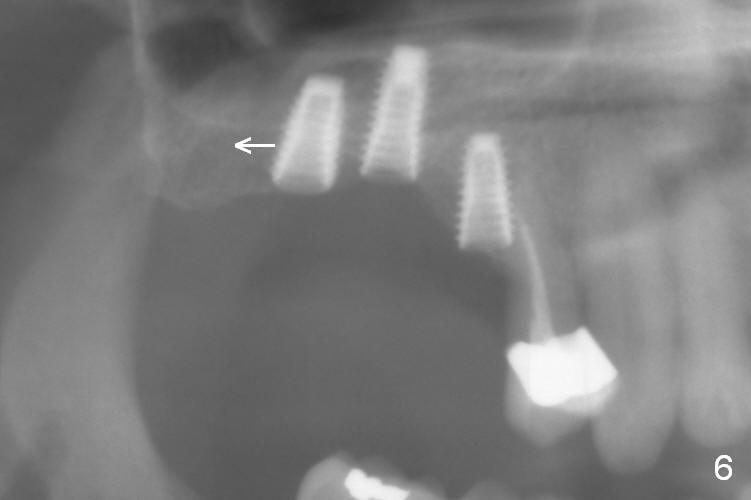

After use of 2.8 mm round bur at #4 for sinus lift, a 4x8.5 mm regular drill is used with resultant sinus membrane perforation at the sinus floor. The latter is repaired with insertion of Osteogen plug prior to place 4.5x8.5 mm implant (Fig.5,6). The similar mistake occurs at #3: after using 2.4/3.7 mm bone expander for 10 mm, a 4x10 mm is used, which also results in sinus perforation, probably sideway, buccally. Trimmed Osteogen plug is placed before a 4.5x10 mm implant is placed with primary stability (Fig.6). The reason for use of the regular drills is to avoid ridge fracture due to under prep.

Since the bone at #2 is soft, the 3.6 mm round drill is used after 2.8 mm one. When a 5x8.5 mm implant is placed, there is no ridge fracture. The implant at #2 should have been placed more distal (Fig.6 arrow).

Insertion torque of the three implants is ~ 50 Ncm. Three long (because of severe vertical bone resorption (Fig.1,6)) abutments are placed immediately for immediate splinted provisional (Fig.7,8 P). The latter should have hemostatic effect. Application of peridontal dressing (D) has additional hemostatic function, exerting pressure the most anterior (Fig.7 between the teeth #5,6) and the most posterior (Fig.8 arrow) incision, where the provisional cannot. Sulcus incision is good to remove subgingival calculus. It seems that chronic periodontits and bruxism play roles in pathogenesis of bone loss.

In fact, these implants seem to heal normally 2.5 months post (Fig.10). After change in abutments at #2 (from 5.5x7(4) to 4.5x5.5(5) mm) and #4 (from 5.5x7(2) to 4.5x5.5(1) mm) and torquing, impression is taken. The implant at #3 appears to be associated with the septal bone (Fig.10 *). There is no apparent bone loss 1 years 4 months post cementation (Fig.11). The patient will return for 14,15 implants.